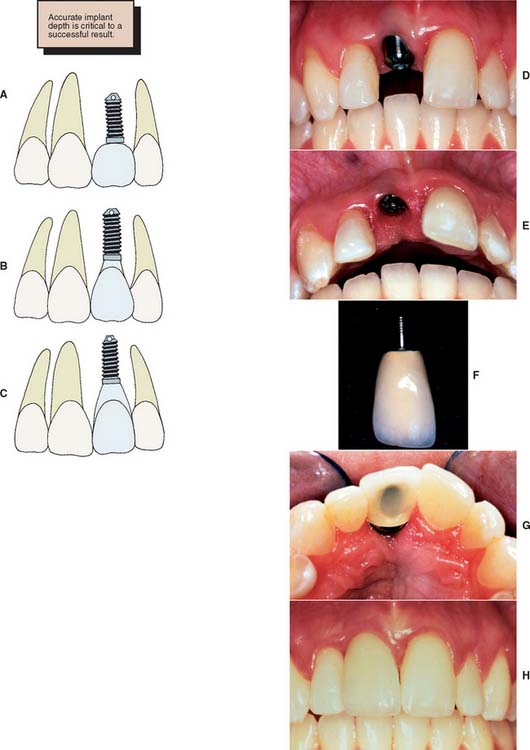

To minimize harmful lateral forces, the long axis of the implant should be positioned in the central fossa of the restoration. This dictates placing the implant accurately in all three planes of space. Superoinferior placement is important to ensure the optimal emergence profile of the restoration. Ideally, the superior surface of the implant should be 2.5 to 3.0 mm directly inferior to the emergence position of the planned restoration, particularly when the restoration is to be located in the anterior esthetic zone (Fig. 13-16).

Fig. 13-16 Superior or inferior positioning may affect crown contours and pocket depth. A, The implant is not placed deep enough. This creates a short, overcontoured crown. B, Placement 2 to 3 mm apical to the tooth emergence position is ideal. C, Placing the implant 4 mm apical to the crown contours may create an excessively deep gingival sulcus. D to H, Clinical example of a properly positioned implant, both facially and apically, which results in good esthetics.

The choice of implant and its superoinferior placement location are modified by the diameter of the intended restoration and can be adjusted for different sizes of teeth. For example, the typical root diameter of a maxillary central incisor is 8.0 mm; the average implant diameter is 4.0 mm. Therefore, a distance of 2.5 to 3.0 mm is needed to make the transition gradually from 4.0 to 8.0 mm. If this is done over too short a distance, the restoration will be overcontoured or look unnatural. In contrast, many mandibular central and lateral incisors are smaller than 4.0 mm at the cementoenamel junction. Therefore, an esthetic restoration on a 4.0-mm implant is impossible. Smaller-diameter implants (about 3.0 mm) are available to allow esthetic restoration in these areas. It is also possible to use a larger implant (5.0 to 6.0 mm) for molar restorations in patients with adequate bone (Fig. 13-17).